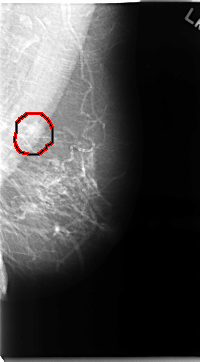

C_0067_1.LEFT_MLO

LEFT_MLO LINES 4696 PIXELS_PER_LINE 2592 BITS_PER_PIXEL 12 RESOLUTION 50 OVERLAY

FILE: C_0067_1.LEFT_MLO.OVERLAY

TOTAL_ABNORMALITIES 1

ABNORMALITY 1

LESION_TYPE MASS SHAPE LOBULATED MARGINS MICROLOBULATED

ASSESSMENT 4

SUBTLETY 4

PATHOLOGY MALIGNANT

TOTAL_OUTLINES 1

BOUNDARY